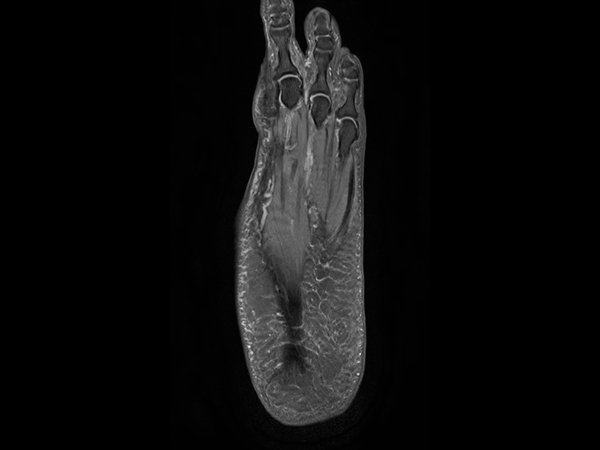

Ankle/Foot imaging post-amputation

Patient with partial amputation of the foot

3D VIEW PDw SPAIR - Axial reformat